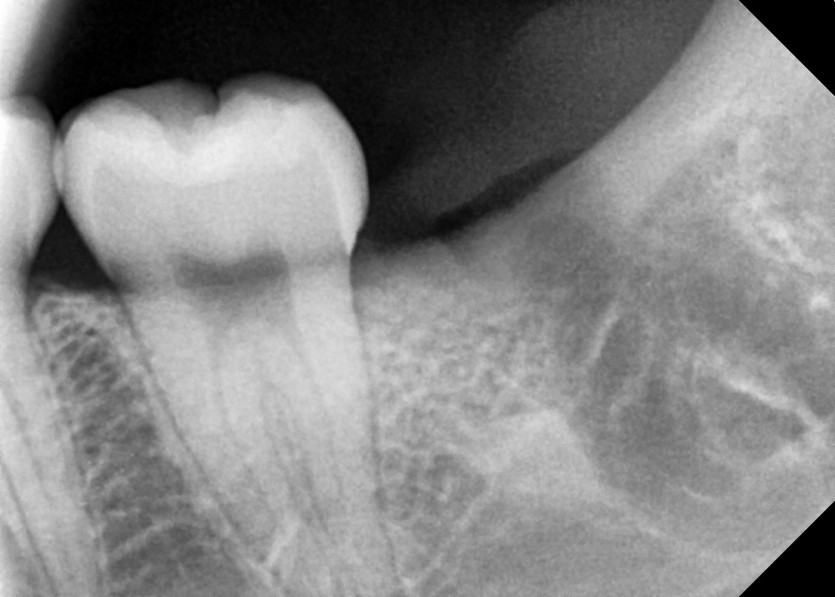

#18,28,38,48 사랑니 발치

구강 외과 전문의가 당일 발치했습니다.